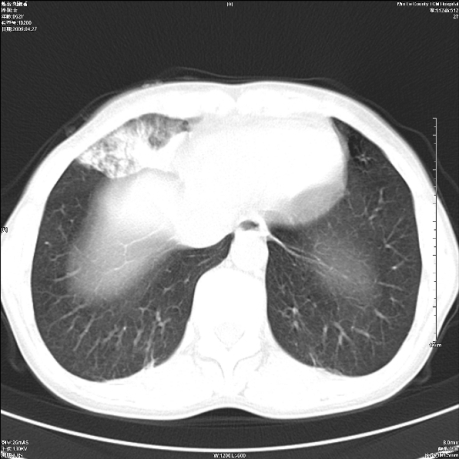

标题: CT19625:女52间断性喀血 [打印本页]

标题: CT19625:女52间断性喀血

考虑右肺中叶感染性病变并右肺中、下叶肺泡积血;建议抗炎、止血治疗后复查。

右肺中叶炎症;右肺中、下叶肺泡积血

右肺中叶支气管扩张并感染或咳血沉积,块右肺中下叶肺泡积血。

右肺中叶慢性炎症伴局部支扩并中下叶肺泡积血。

考虑右肺中叶感染性病变并右肺中、下叶肺泡积血。建议治疗后复查。